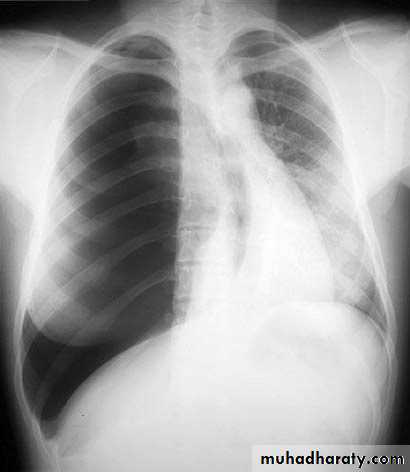

Slide 18. 1- comment on the xray2- the best response to you for urgent treatment